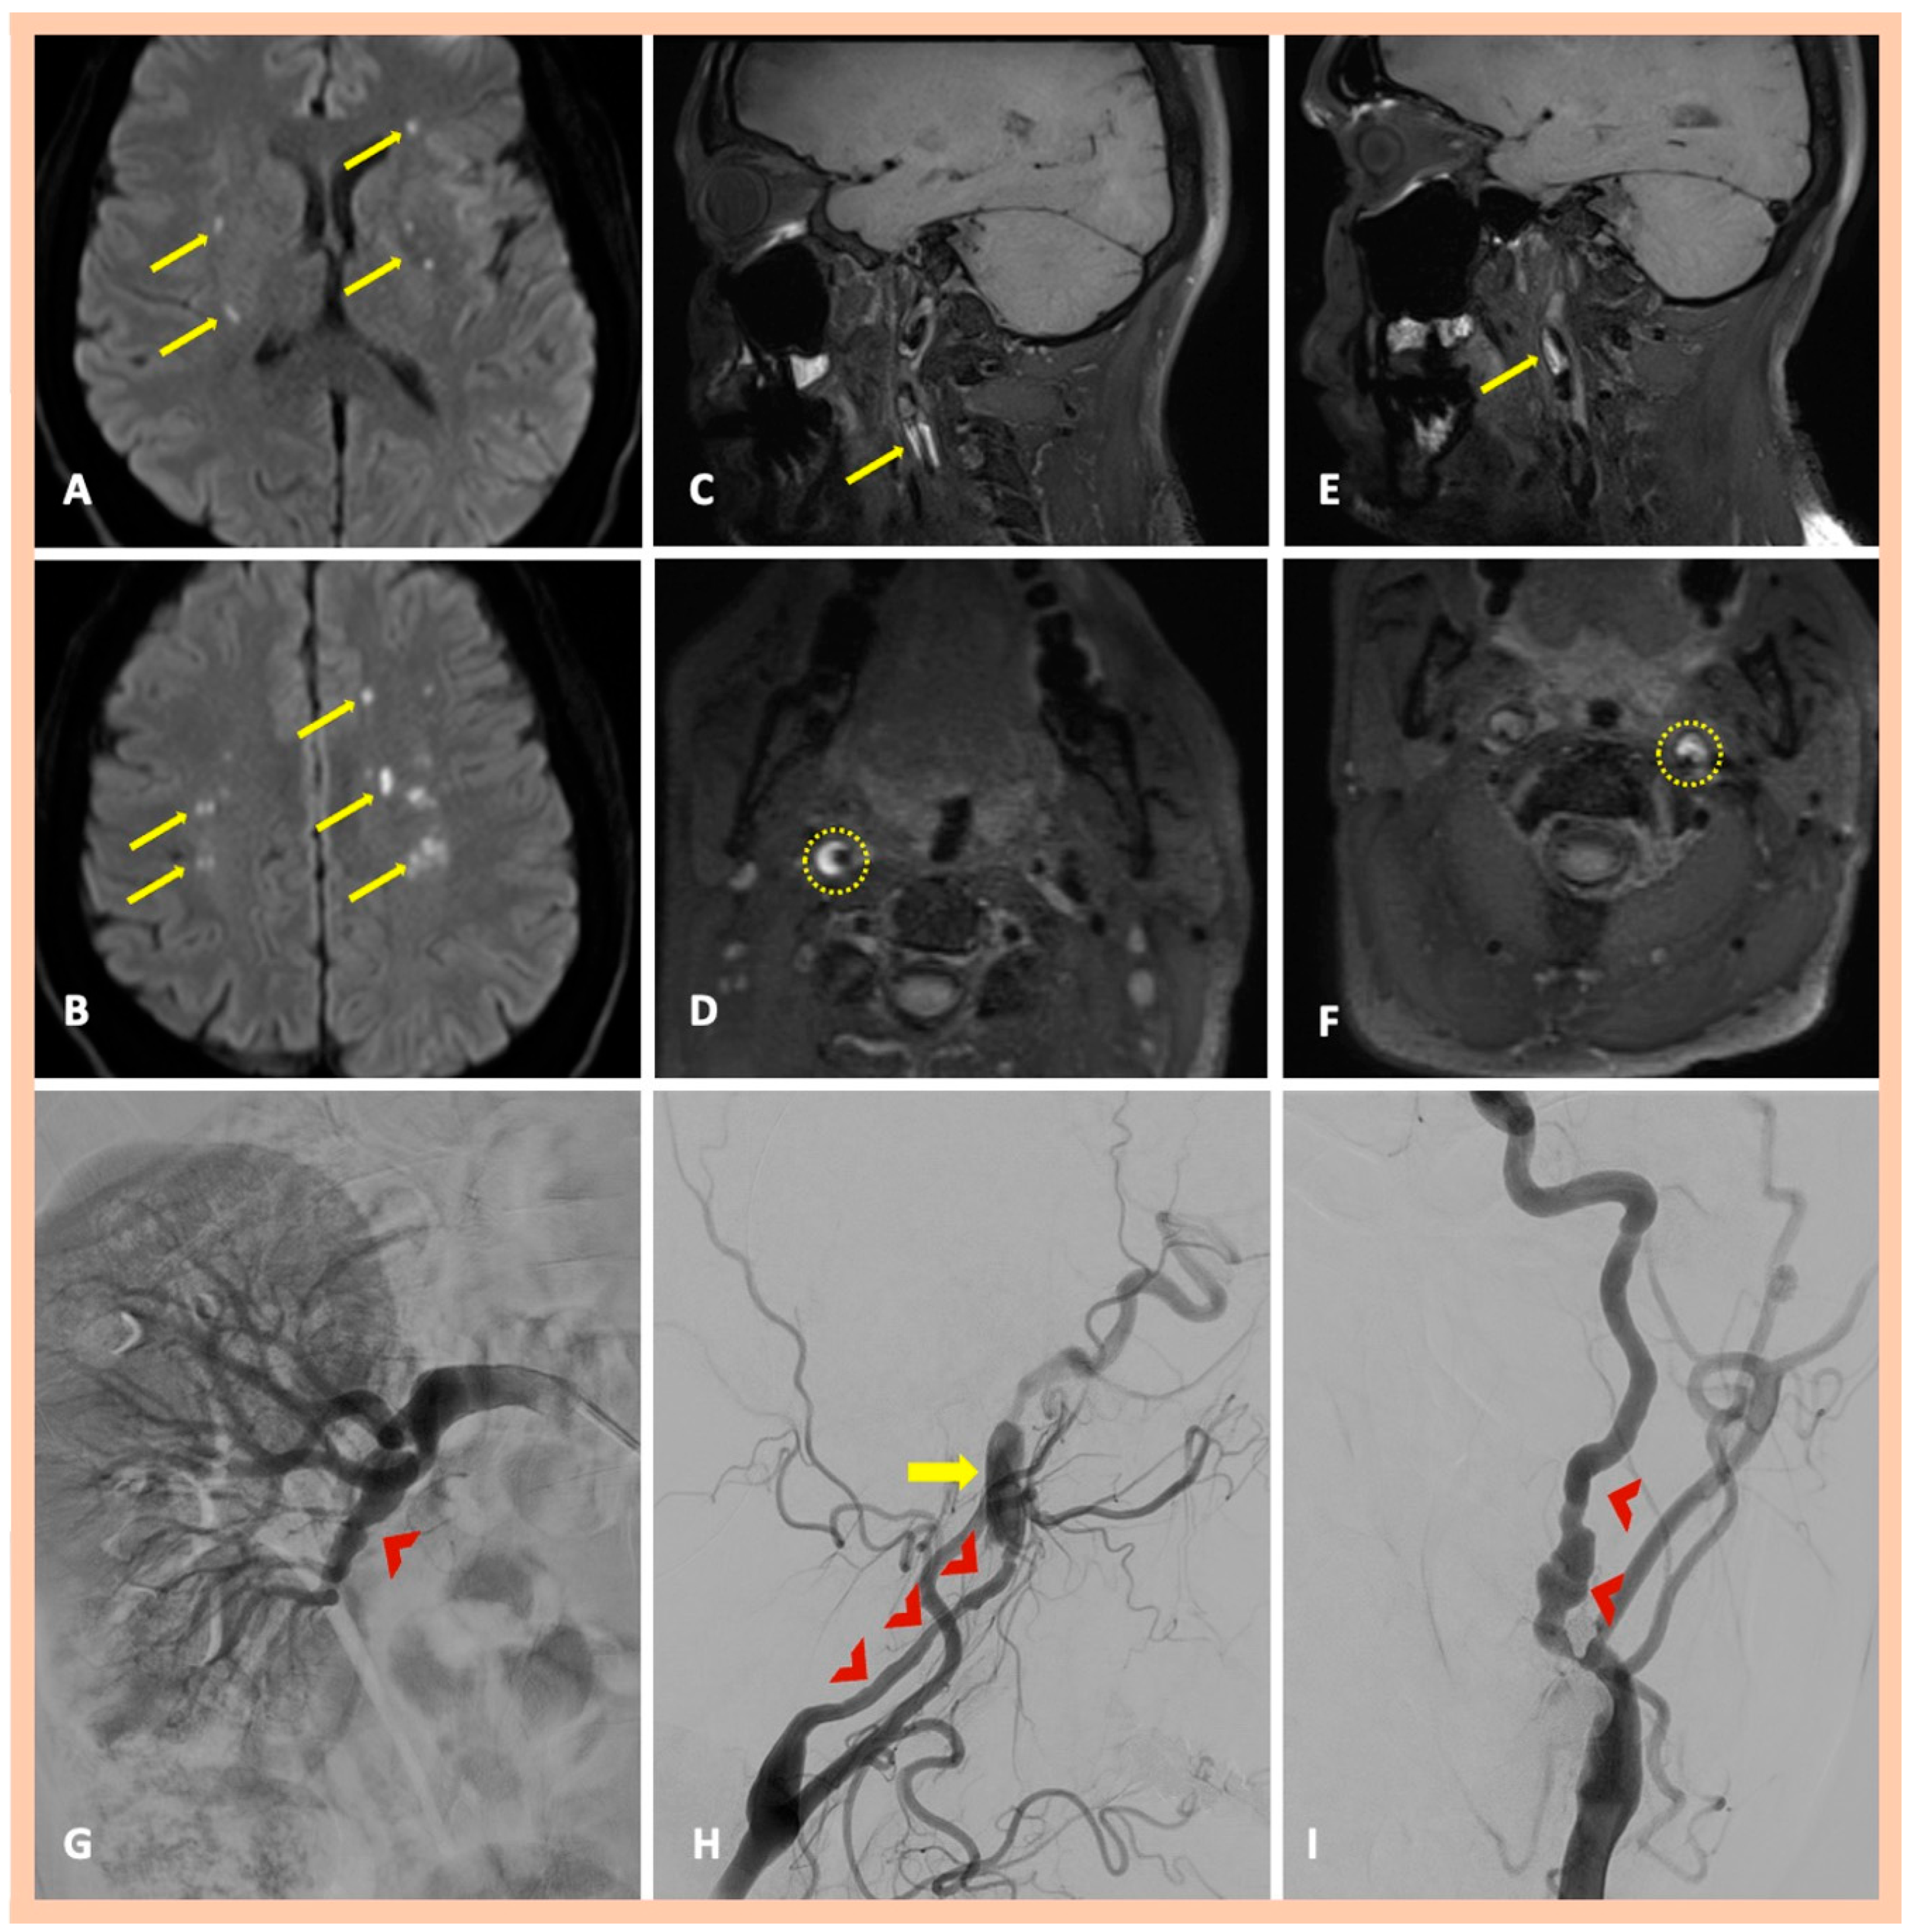

| Pat. #7 | Yes—multiple ischemic lesions in different arterial territories | Stenoses along the cervical segments of the right and left ICA. Characteristic “string-of-beads” appearance along the cervical segment of the left ICA | Intramural hematoma along the cervical segment of the right ICA. Intramural hematoma along the cervical segment of the left ICA, combined with the typical beaded appearance | DSA confirmed the findings and also revealed a focal stenosis of the right renal artery | Asymptomatic right and symptomatic left ICA dissections | 2 | Yes—focal stenosis of right renal artery |

| Pat. #10 | Bilateral multiple ischemic lesions in different arterial territories | Stenosis along the distal cervical and proximal petrous segments of the right ICA. Stenosis along the distal cervical and proximal petrous segments of the right ICA. | Chronic intramural hematoma along the distal cervical segment of the right ICA. Intramural hematoma along the cervical and proximal petrous artery segments of the left ICA | Confirmed MRA findings CT revealed elongated styloid processes bilaterally, indicative of Eagle syndrome | Symptomatic right and left ICA dissections | 2 | No |